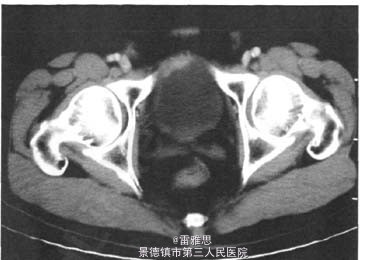

3、查体:未见明显阳性体征 4、辅助检查:泌尿系B超示:膀胱占位。盆腔CT示:膀胱右前壁增厚,考虑占位。胸片及肝、胆、胰、脾B超未见异常。胃镜及肠镜未见占位。膀胱镜检:膀胱右前壁见絮状新生物。膀胱镜病理诊断:印戒细胞癌。

5、诊断:原发性膀胱印戒细胞癌 6、处理:行“剖腹探查术”,打开腹膜,探查见膀胱顶部占位,质硬,表面欠光滑。与周围组织分界欠清,腹膜壁层、肠系膜及大网膜见多处转移灶,取腹膜壁层及大网膜转移灶送术中快速病理示:脂肪结缔组织内见黏液细胞癌。因肿瘤已广泛转移,未行原发灶手术切除。术后病理:纤维结缔脂肪组织内浸润性或转移性印戒细胞癌。